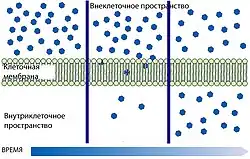

Свободная диффузия

Самой простой формой транспорта через ГЭБ является свободная (или пассивная) диффузия. Она может осуществляться как через клеточные мембраны эндотелиоцитов, так и через плотные межклеточные контакты. Для диффузии веществ движущей силой является разница концентраций. Диффузия веществ пропорциональна градиенту концентраций в кровеносном русле и ткани мозга. Для неё не требуется затрат клеточной энергии[120].

Липофи́льные структурные элементы клеточной мембраны, а также плотные межклеточные контакты снижают количество веществ, которые могут свободно диффундировать через ГЭБ. Проницаемость ГЭБ напрямую зависит от липофильности каждого конкретного вещества[121].

Проницаемость ГЭБ также зависит от молярной массы вещества. Молекулы с массой более 500 г/моль не могут диффундировать через ГЭБ. В то же время ГЭБ не является механическим барьером, который свободно пропускает молекулы меньшего размера и не пропускает большего. Процесс клеточной диффузии является динамическим, при этом он легче для веществ с молярной массой 200 г/моль, чем для веществ с 450 г/моль[41][122]. Чем липофильнее и меньше вещество, тем легче оно диффундирует через клеточную мембрану[6].

Немецким биофизиком Германном Тро́йбле в 1971 году была высказана гипотеза о транспорте молекул с низкой массой через клеточную мембрану. Согласно ей они проникают в клетку через небольшие промежутки между цепями жирных кислот двойного слоя мембраны. Эти промежутки изменчивы, их образование не требует клеточной энергии[123][124][125][126]. Теория Тройбле была спектроскопически доказана в 1974 году[127][128].